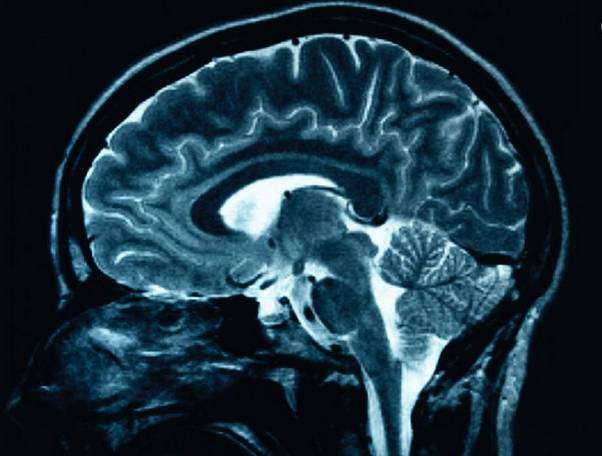

特别是以下情况,如脑外伤或自发性脑出血,脑梗塞,脑炎等原发或继发性脑病,缺血缺氧性脑病等。在这里主要阐述放血疗法对以上病症引起的患者头痛头晕,烦躁不安,高级脑功能缺失或低下,昏迷或兴奋性不高等情况的调节作用。在对其泻热消瘀、活血通络、开窍启闭、护脑醒神功效的手十二经井穴刺络放血疗法进行深入研究中表明,这种疗法对脑血流有双向调节作用,可明显改善缺血区脑组织的急性缺氧状态,缓解乳酸堆积造成的酸中毒,加強腦細胞膜的通透性,减轻因细胞外钾、钠离子失衡引起的脑水肿的发展,起到保护脑细胞,急救中风的作用。

另外在现代临床研究中表明,人体血液中一氧化氮含量的变化密切影响着人们的情绪和认知,脑细胞的抑制和兴奋,而血液中一氧化氮含量的调节最好的方法就是对血管内皮的刺激。

而放血疗法就是通过点刺穴位血管而使血液中生成一氧化氮,血管内皮素,血栓凝吸收因子等物质。而这些物质的生成对血管的收缩与舒张,情绪意识的影响等起着非常重要的作用,再加上手足末端的井穴本身刺激量就比较强,所以使这种双向调节作用更加的直接迅速且持续时间也比较长。